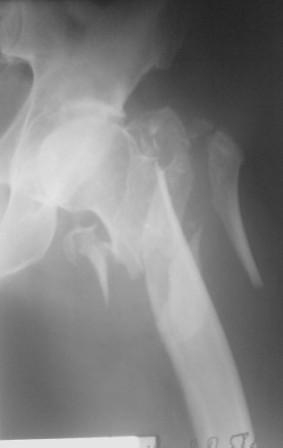

Уважаемые коллеги. В наше отделение поступил пациент, мужчина 60 лет, с закрытым

оскольчатым чрезвертельным переломом левого бедра. Хотелось бы знать Ваши сооброжения по

поводу лечения данного перелома. Снимки прилагаю.